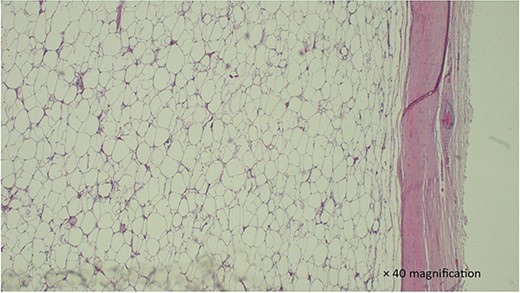

Histology revealed mature adipocytes without cytological atypia or separations, confirming the diagnosis of mesenteric lipoma (Fig. 2). The patient was discharged on the third postoperative day and had an uneventful recovery, with no abdominal symptoms reported during 8 months of follow-up.

H & E stained section show a section with proliferation of well-circumscribed mature adipocytes without atypia. which is well circumscribed.

The diagnosis of lipoma is confirmed by histopathological examination of the lipomatous tumor [5, 11]. It resembles normal adipose tissue under the microscope, with cytoplasmic lipid vacuoles laden mature fat cells of relatively uniform size, without cytological atypia [5]. Atypical and bizarre spindle cells and floret-like giant cells, with pleomorphic and hyperchromatic nuclei, with a sclerotic background, are suggestive of the possibility of liposarcoma [5]. While fewer than 50 cases of mesenteric lipoma have been reported in English literature, mesenteric liposarcoma has not been reported [7].